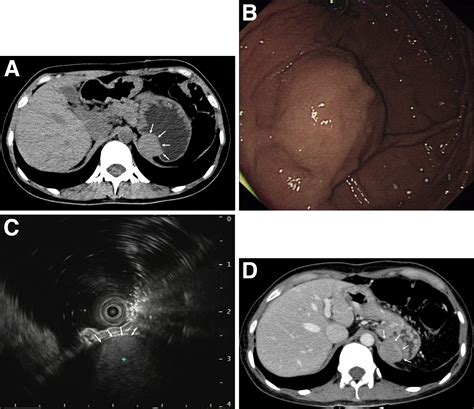

Discovering a mass in stomach can be concerning. Learn about potential causes, common symptoms like abdominal pain or bloating, and why timely diagnostic testing is essential. Understand when to consult a gastroenterologist for an accurate medical diagnosis, imaging scans, and effective treatment options to address abnormal growths or tumors in the digestive tract.